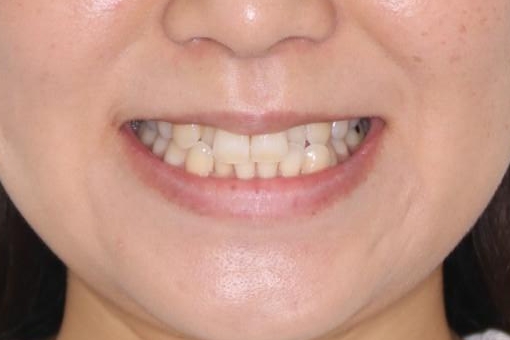

【インビザライン】前歯の凸凹をなおしたい

- 前歯の凸凹を主訴に来院されました。

上顎の急速拡大を行なったのちインビザラインにて治療を行なっております。

今回のケースは後戻りのリスクを低くし、またディスキング量を減らすために上顎の急速拡大を行なっております。